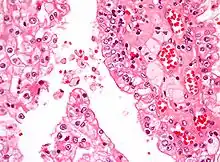

| Micrograph showing the most common type of kidney cancer (clear cell renal cell carcinoma). H&E stain. | |